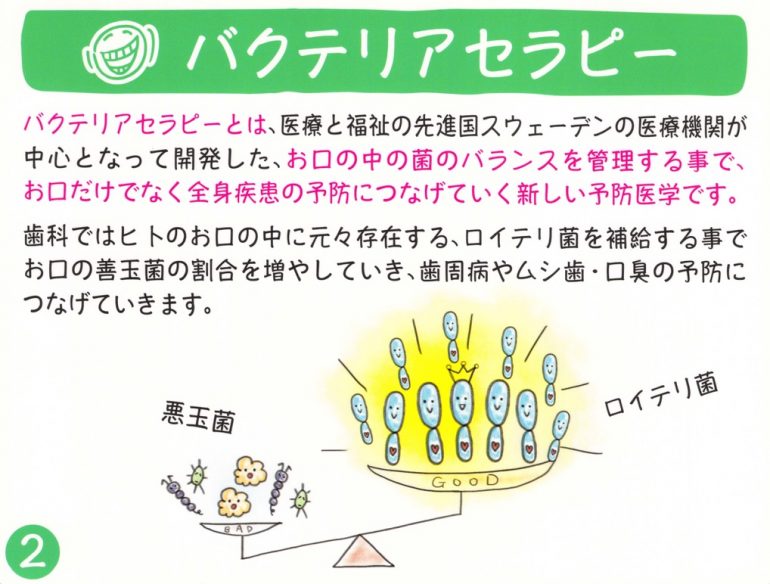

感染症予防で注目されているバクテリアセラピーとは

バクテリアセラピーは、予防医学の先進国のスウェーデンで開発された最先端の予防医学技術です。

優れた善玉菌を摂取することで体内の菌のバランスを整え、体質を変えていく細菌療法のことを言います。世界100カ国と地域の医療機関に導入されています。

元々ヒトの体内に住んでいる善玉菌を摂取するため、副作用など人体に害を与えることがなく、新生児から高齢者の方までカラダに優しく安全が確立された予防方法です。

通常の歯科治療やメンテナンスに加え、母乳由来の乳酸菌であるロイテリ菌を摂取していただくだけで、口腔内の病原菌の減少、胃や腸内環境の改善、授乳中では母乳の質の改善も認められいます